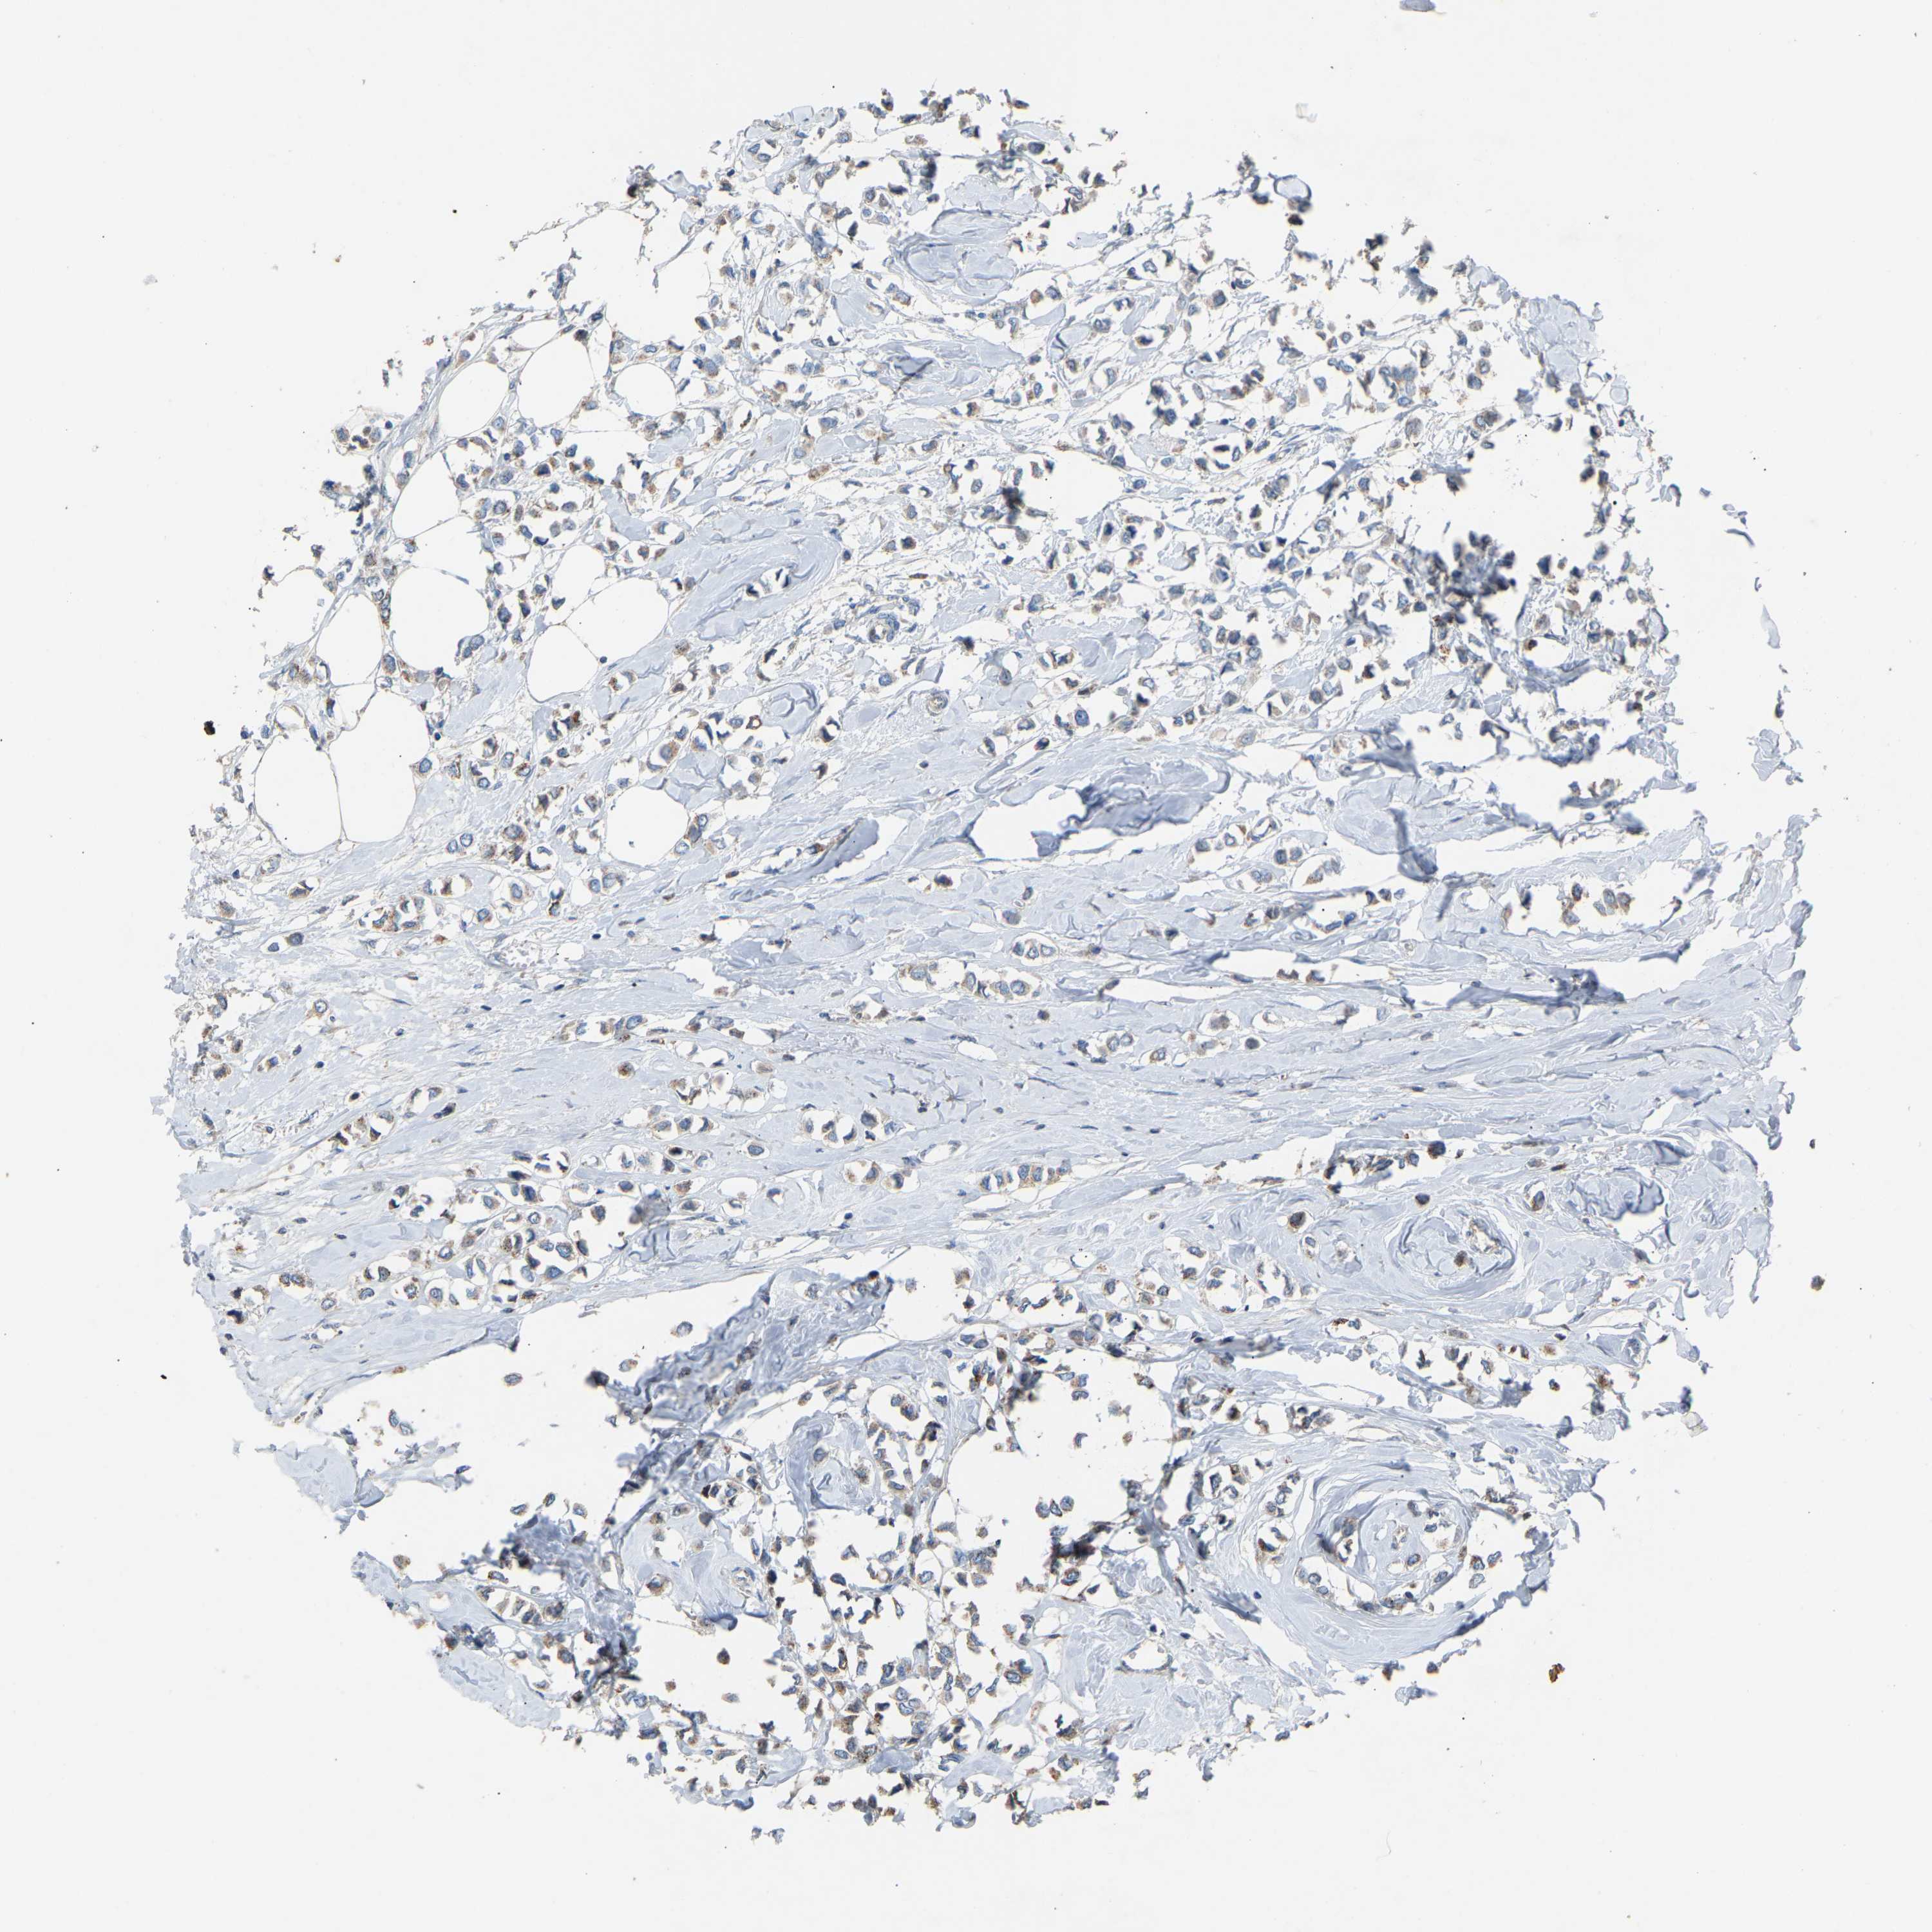

CANCER BREAST CANCER Show tissue menu

BRCA TCGA BRCA VALIDATION PROTEIN EXPRESSION

ANTIBODIES

AND

VALIDATION